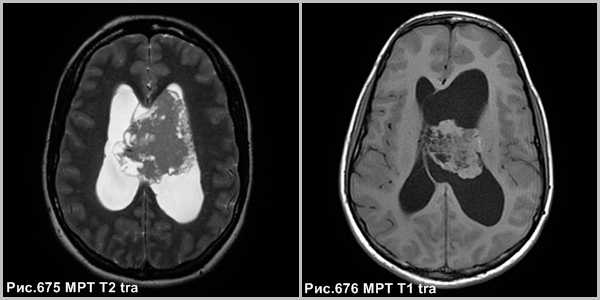

Центральная нейроцитома - кистозно-солидное объёмное образование, расположенное в боковом желудочке, связанное с прозрачной перегородкой, сопровождающееся расширением желудочковой системы (рис.677, 678).

На КТ и МРТ нейроцитомы - отграниченные образования, смешанной плотности, часто содержат кальцинаты (в 50-70% случаев) и кисты. В большинстве случаев опухоль сопровождается гидроцефалией обструктивного генеза.

Опухоль может инфильтрировать стенку бокового желудочка. В 20% случаев имеются внутриопухолевые кровоизлияния. Располагаются в просвете боковых желудочков головного мозга с тенденцией к локализации в области прозрачной перегородки и отверстия Монро.